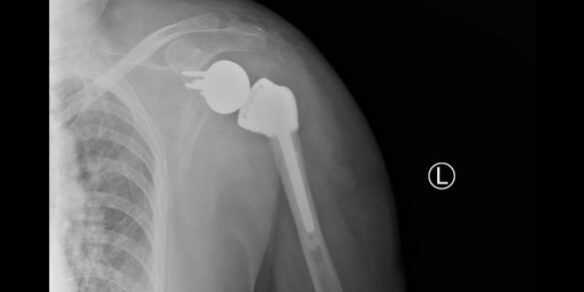

术后患者状况良好,第二天即可开始下地运动,肩枢纽也可以做一些简单的前后运动,X光片显示肩枢纽假体在位良好,目前患者已康复出院。